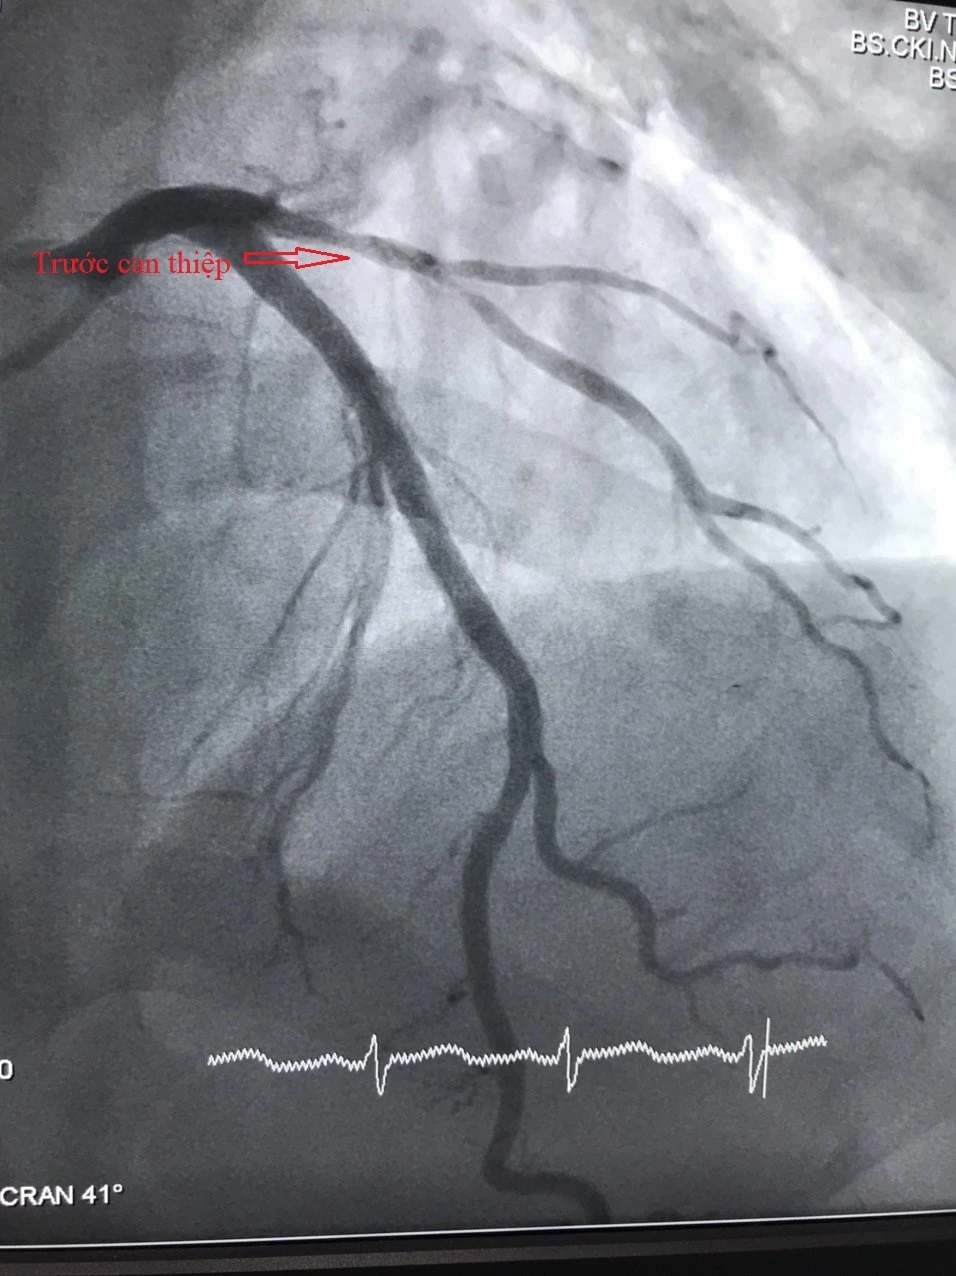

Hình ảnh tổn thương mạch vành trước và sau can thiệp. Ảnh: BVCC 1 Hình ảnh tổn thương mạch vành trước và sau can thiệp. Ảnh: BVCC 2

Hình ảnh tổn thương mạch vành trước và sau can thiệp. Ảnh: BVCC

Qua khám và tiến hành xét nghiệm bác sĩ xác định bệnh nhân bị nhồi máu cơ tim cấp, động mạch liên thất trước (LAD) bị thâm nhiễm, hẹp 80%-90% nhánh chéo 1 và có chỉ định can thiệp mạch vành cấp cứu. Các bác sĩ đã tiến hành can thiệp mạch vành cho bệnh nhân bằng cách nong bóng và đặt stent phủ thuốc với thời gian 30 phút.